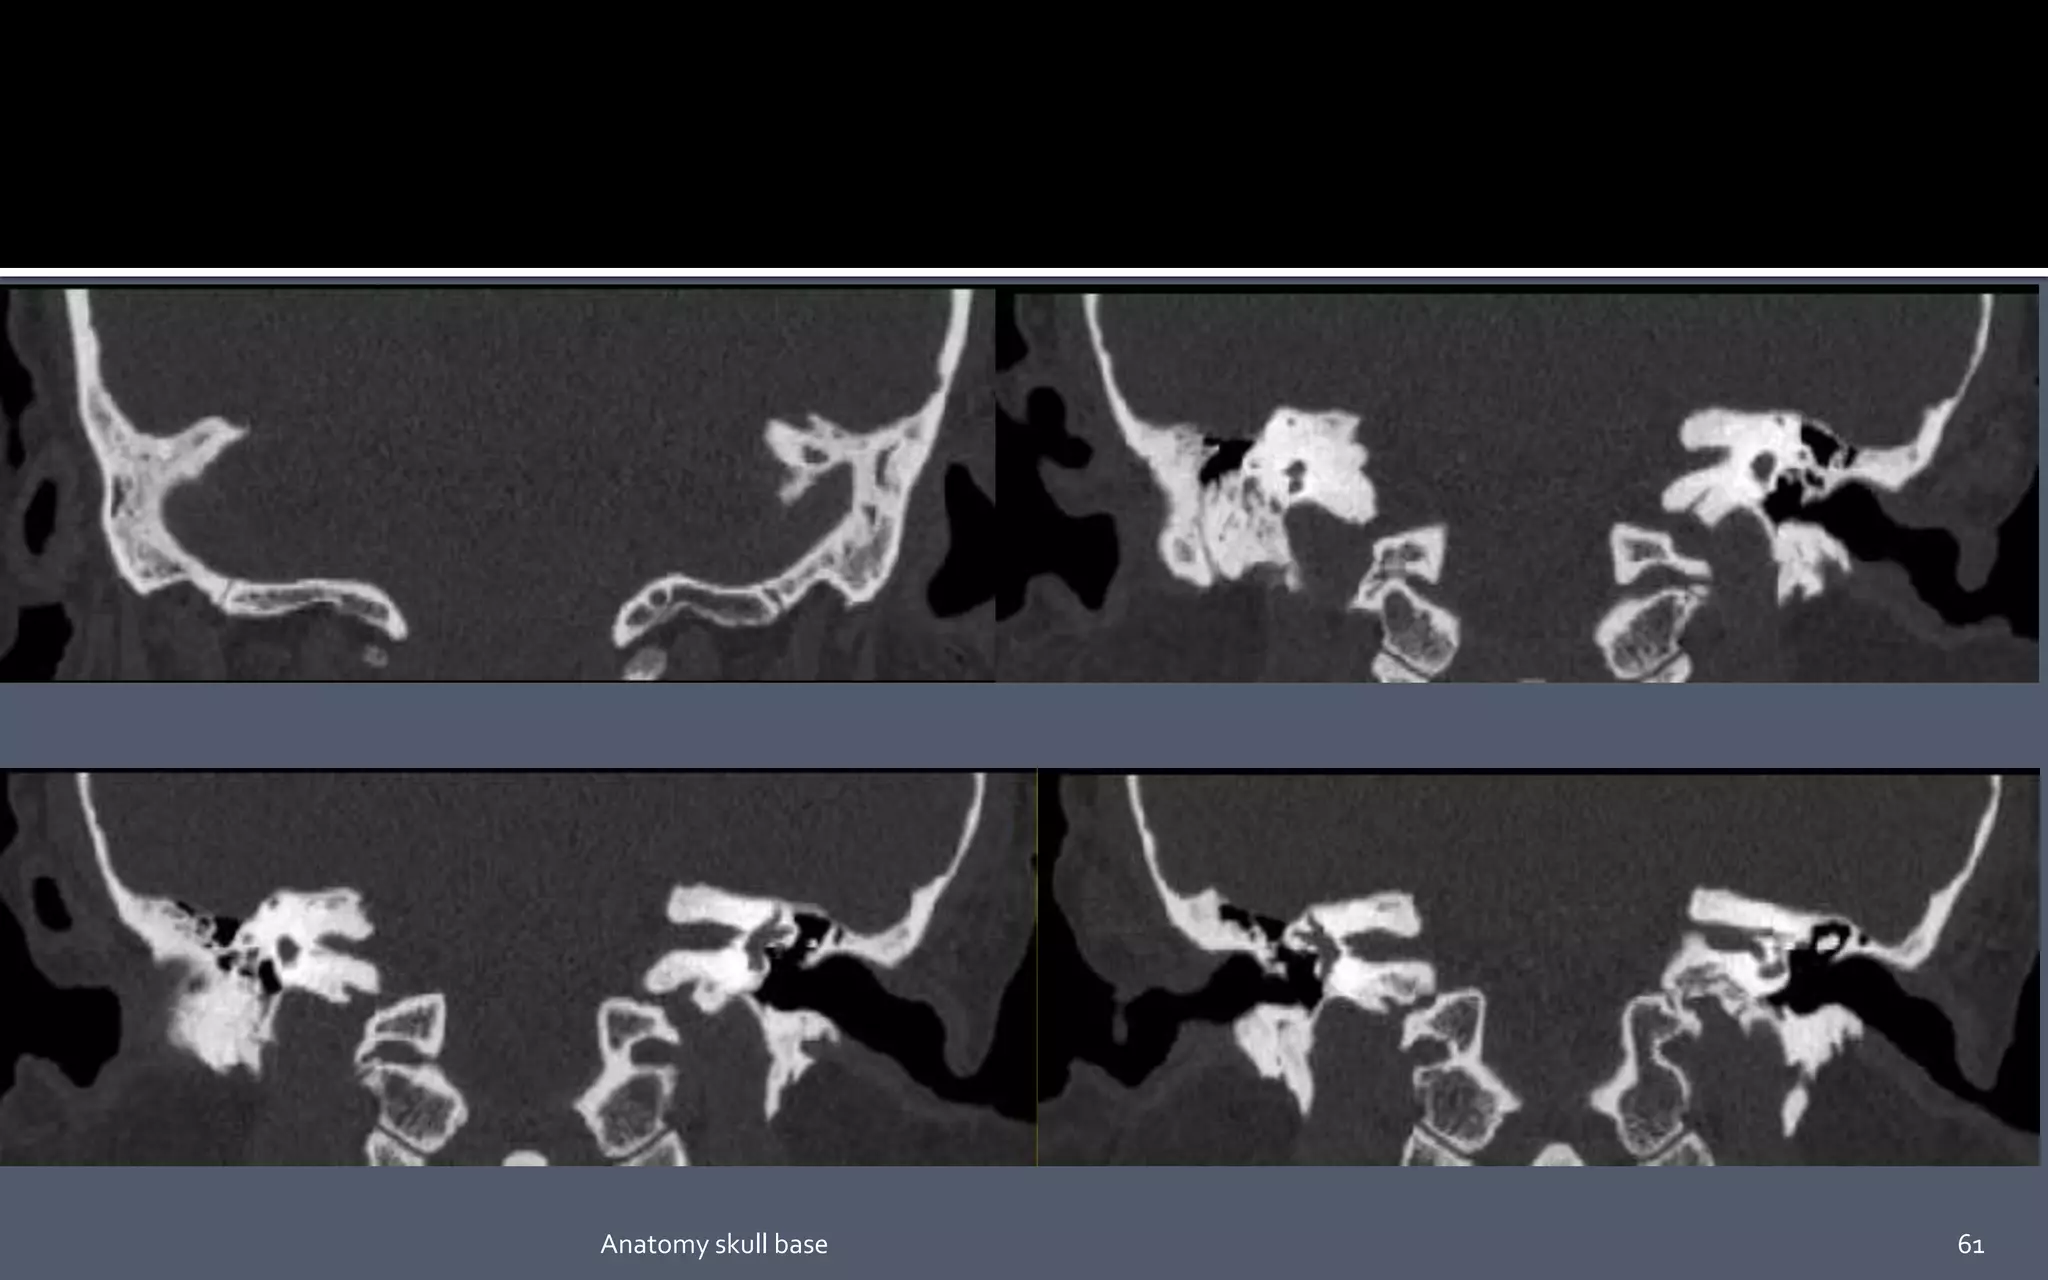

61Anatomy skull base

• #20 The medial red lines pass in the medial aspect of the petroclival synchondrosis (long white arrows). The lateral red lines pass immediately lateral to the foramen ovale. (short white arrow).

• #49 1. Petro-occipital fissure. 2. Petrosphenoid suture. 3. Tympanomastoid suture. 4. Sphenosquomaous suture. 5. Sphenozygomatic suture.